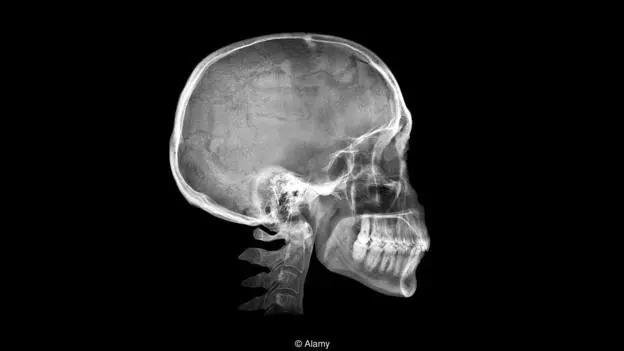

这种隆起状的特征,也被称为“枕外隆突”,出现在颅骨后下部,刚好在颈部上方,如果你具有枕外隆突,那很可能用手指就能触摸到它——或者如果你秃顶的话,甚至可以从后面看到它。

直到不久前,枕外隆突还被认为是极其罕见的特征。1885年,当科学家第一次研究这个隆起时,法国著名科学家保罗·布罗卡抱怨称,居然还有人给它取名字,他不喜欢枕外隆突,因为他研究了那么多标本,却没有真正看到任何有这种情况的。

而在分析了一千多张从18岁到86岁的人头骨X光片后,科学家的发现令人震惊。这一特征的出现比预想的普遍得多,而且在最年轻的年龄组更为普遍:18至30岁的人群中,每四个人中就有一个出现枕外隆突。为什么会这样呢?我们应该担心吗?